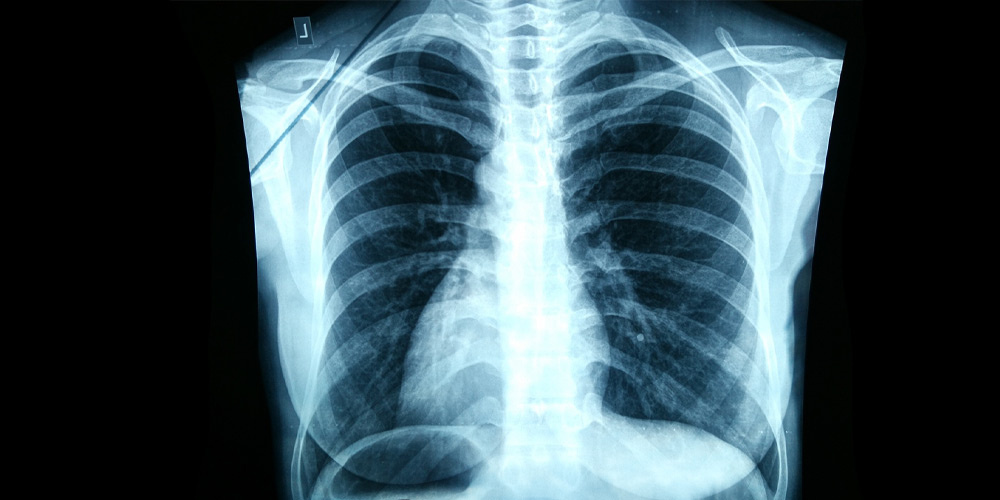

Рентген используют для диагностики большого количества заболеваний. В этот список входят переломы костей, опухоли, заболевания сердца и лёгких. Флюорографию применяют для массового обследования населения на предмет выявления туберкулёза и других заболеваний дыхательной системы. Поэтому с помощью флюорографии исследуют только легкие.

Рентгеновские снимки обладают более высоким разрешением и детализацией, что позволяет врачам видеть даже незначительные изменения в тканях и органах. Флюорография же предоставляет общую картину состояния исследуемой области. На флюорографическом снимке видны тени размером от 5 мм, поэтому мелкие объекты такой способ диагностики распознать не позволит.